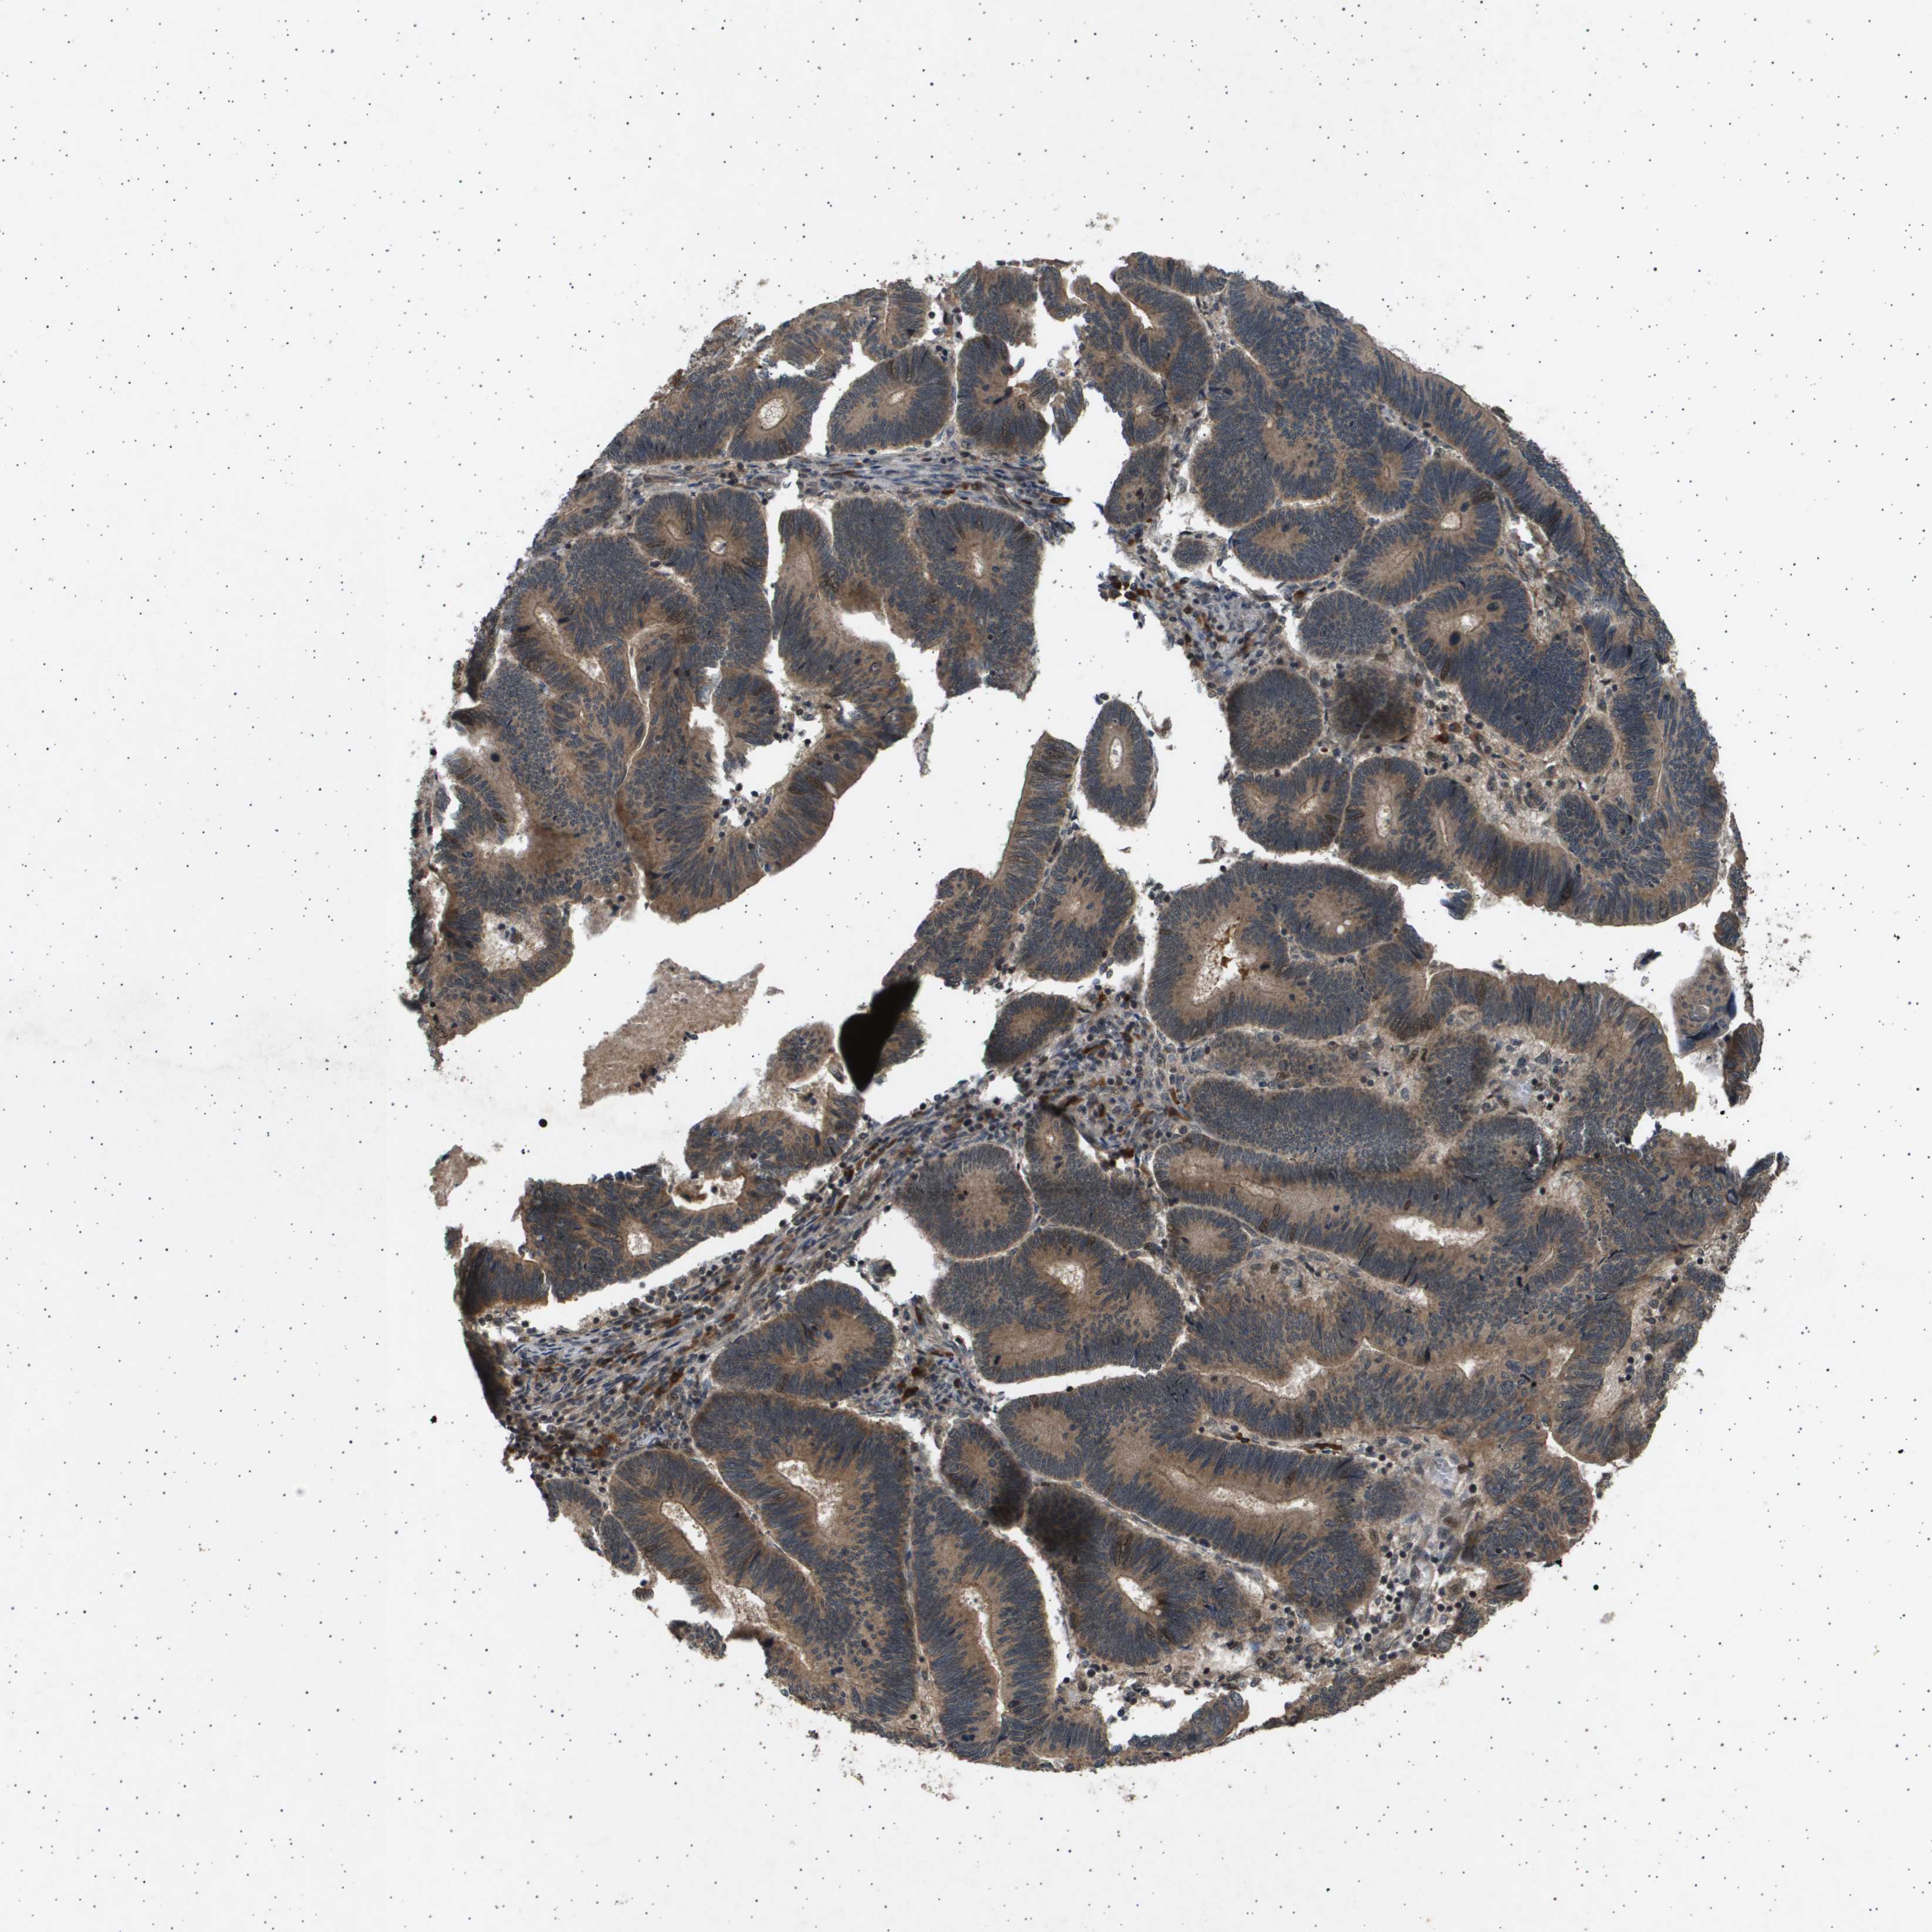

PANCREATIC CANCER - Protein expressioni

A mouse-over function shows sample information and annotation data. Click on an image to view it in a full screen mode. Samples can be filtered based on level of antibody staining by selecting one or several of the following categories: high, medium, low and not detected. The assay and annotation is described here.

Note that samples used for immunohistochemistry by the Human Protein Atlas do not correspond to samples in the TCGA dataset.

Antibody stainingi

Antibody staining in the annotated cell types in the current human tissue is reported as not detected, low, medium, or high, based on conventional immunohistochemistry profiling in selected tissues. This score is based on the combination of the staining intensity and fraction of stained cells.

Each image is clickable and will lead to virtual microscopy that enables deeper exploration of all samples and also displays staining intensity scores, fraction scores and subcellular localization as well as patient and tissue information for each sample.

Antibody HPA017869

Staining

High

Medium

Low

Not detected

Intensity

Strong

Moderate

Weak

Negative

Quantity

>75%

75%-25%

<25%

None

Location

Nuclear

Cytoplasmic/membranous

Cytoplasmic/membranous,nuclear

Adenocarcinoma, NOS